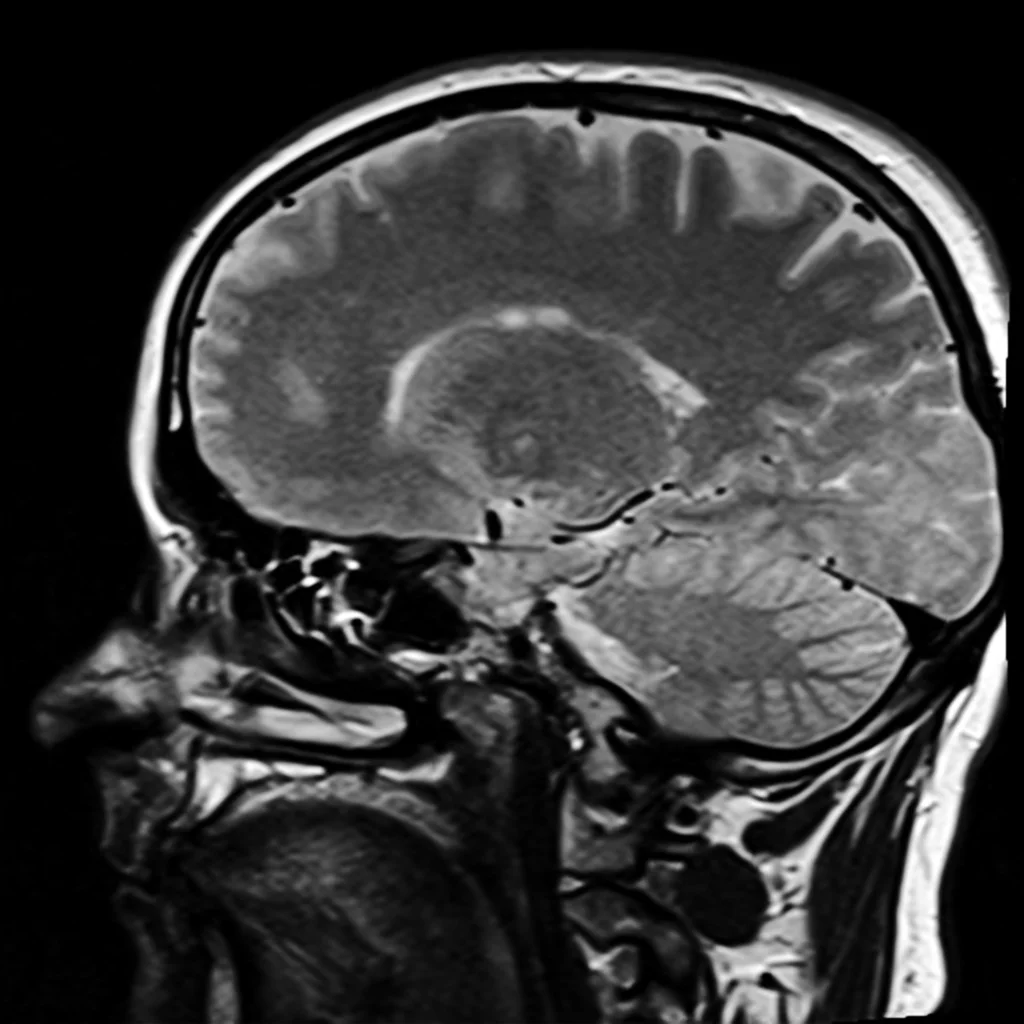

I sat, nervously watching the clock. It had been 21 hours since my MRI and they told me they would call me with the results within 24 hours.